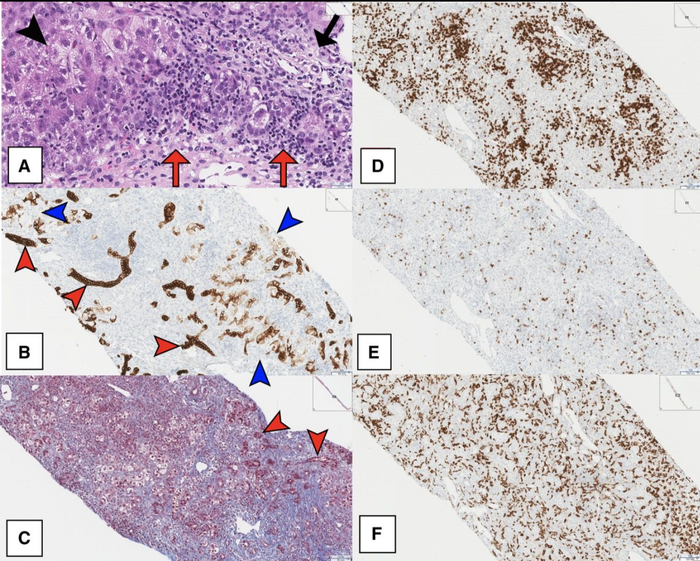

患儿的肝活检显示她出现了急性亚大面积肝坏死、小叶塌陷和严重的混合炎性浸润,主要由CD3+T淋巴细胞导致。

诊断性肝活检突出大量CD3+T细胞浸润和急性亚大面积坏死。A)急性亚大面积肝细胞坏死和塌陷(黑色箭头),伴有替代性纤维化、再生性变化和以单核为主的炎症(红色箭头),与代偿性增生性再生结节(非炎症区,黑色箭头)交替出现(H&E染色)。B)残余胆管(红色箭头),在小叶实质中具有双表型肝细胞(蓝色箭头),在CK7免疫染色上很明显。C)三色染色突出大量坏死后纤维化(蓝色)、再生肝细胞(浅红色)和胆管(红色箭头)。D)CD3免疫染色突出显示主要是CD3+T淋巴细胞浸润。E)CD79a免疫染色显示混合的B淋巴细胞。